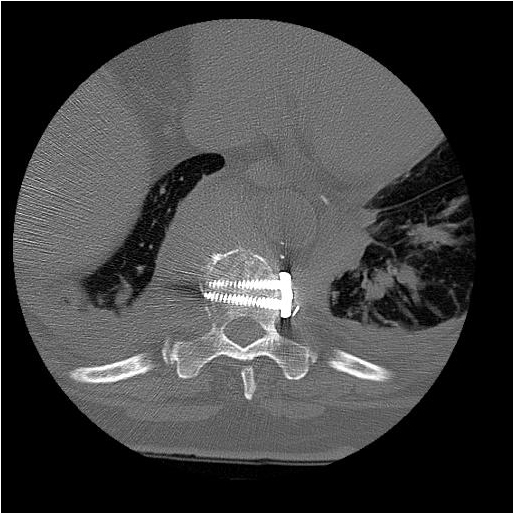

After completion of the spinal procedure, reorientation of the thoracic surgeon by the spinal surgeon is performed, including visualization of the implanted hardware and an explanation of the procedure that was performed (Figures 9a-c). Hemostasis is secured, the chest irrigated, and the posterior mediastinum is inspected for lymph leak (the presence of a CSF leak must be ruled out by the spine surgeon prior to this point in the operation). The diaphragm, if mobilized, is reattached to the fascia of the posterior chest wall with interrupted horizontal 0 prolene sutures or is anchored around the rib. A 28 Fr chest tube is placed in the posterior mediastinum and the chest is closed in a standard fashion. Postoperative spine imaging is necessary to demonstrate adequate position of the hardware and correction of the vertebral defect (Figures 10a-e, Video).

| Figure 10a-e: CT of spine after fixation | Figure 10b | Figure 10c |

| Figure 10d | Figure 10e |